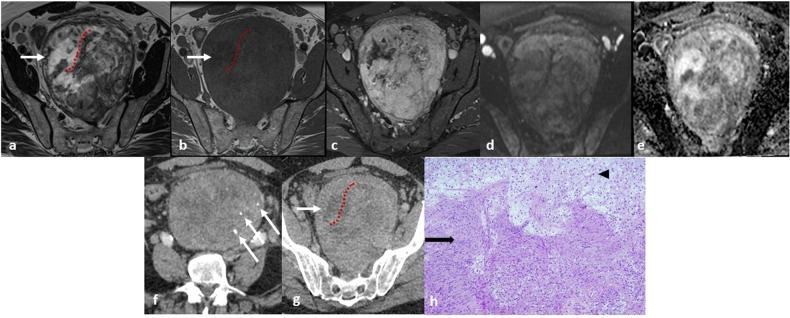

Benign nerve sheath tumors presenting as solitary retroperitoneal masses (RBNSTs) pose a complex diagnostic challenge for multidisciplinary teams regarding differential diagnosis, staging, and treatment planning. This article reviews the role played by different imaging techniques in assessing RBNSTs and elucidates their typical pathological features with a particular emphasis on the correlation between imaging and histological findings. Furthermore, some examples of retroperitoneal tumors that merit consideration in the process of differential diagnosis based on cross-sectional investigations (CSIs) are reported. The correlation between tissue architecture and appearance on imaging can help increase the accuracy of differential diagnosis with other retroperitoneal neoplasms at CSIs.

This educational review critically examines the correlation between imaging and histological features in solitary retroperitoneal benign nerve sheath tumors, offering valuable insights for improving the accuracy of differential diagnosis in clinical radiology.

RBNSTs are challenging to diagnose because they lack specific radiological features. Differential diagnosis of RBNSTs from other retroperitoneal neoplasms on imaging is complex. Surgical removal of RBNSTs is recommended for an accurate diagnosis.